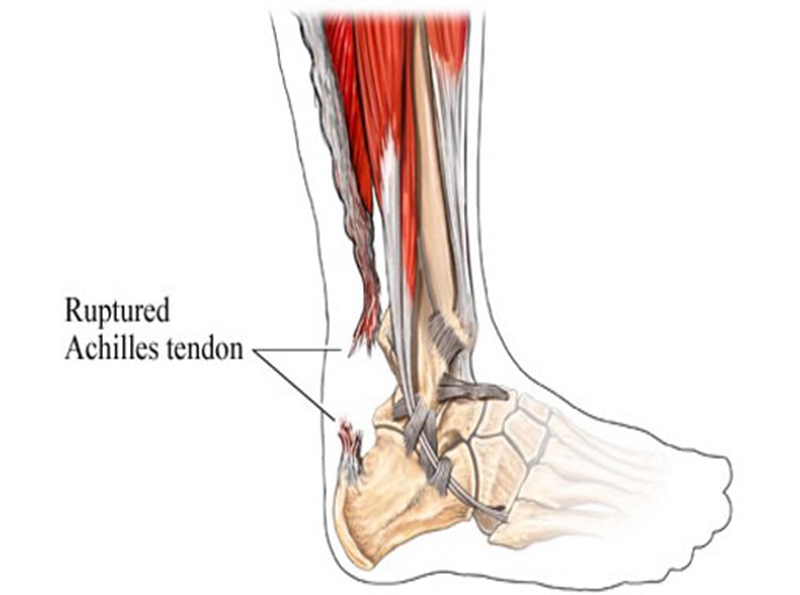

跟腱是人体最长、最强壮的肌腱,起于腓肠肌和比目鱼肌,止于跟骨结节,长约15cm。它在腱的背侧约有4-8层润滑层,位于深筋膜与腱组织之间,每层有独自的营养血管。具有踝关节跖屈,完成脚尖站立、正常走路、跑、跳、上下楼梯等动作的功能。

跟腱断裂容易发生于偶尔参加运动的中年人,所以也称这类人为“周末运动员”。踝在过伸位突然用力,断裂多发生在跟腱止点上方2~6cm,因为跟腱自上而下逐渐变窄增厚,跟骨结节上方2~6cm处最窄,此处最薄弱。

症状:跟腱部肿胀、疼痛,足跖屈无力。患者经常诉脚后跟被人踢了一脚,或棒击感。

查体:跟腱连续性中断,局部凹陷,跖屈力量明显减弱,提踵试验阳性,Thompson试验阳性。